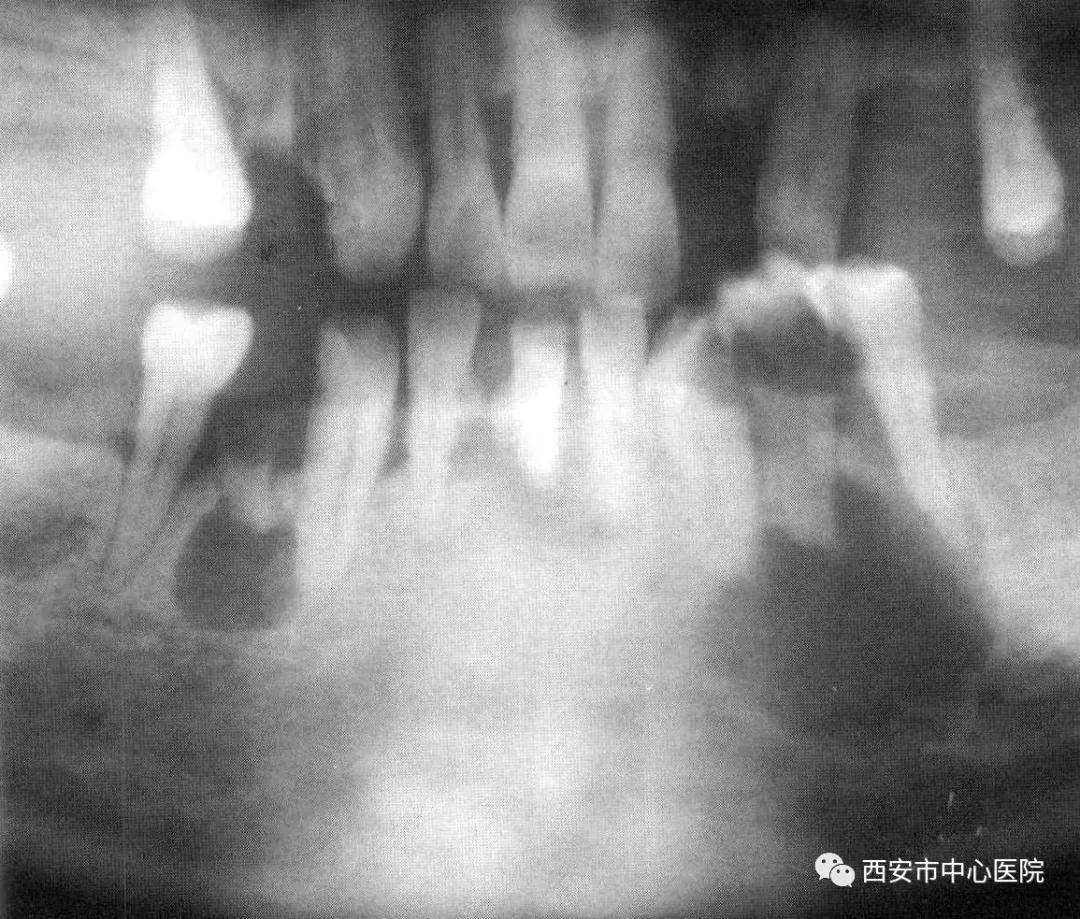

严重的根尖疾病

文章图片

有些根尖疾病发展到很严重的时候 , 是无法通过简单的根管治疗或根尖区手术解决的 。 比如巨大的根尖囊肿 , 因为无明显症状 , 又无法通过上述方法治疗 , 常被患者所忽视 , 它会慢慢的增大 , 侵袭你的颌骨 , 有时甚至会导致颌骨骨折 。